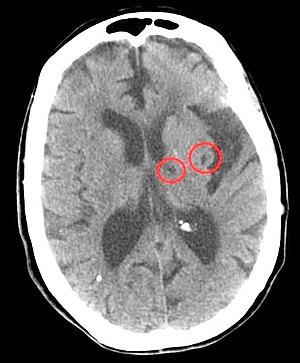

CT of lacunar strokes.jpg

CT scan of two lacunar strokes.